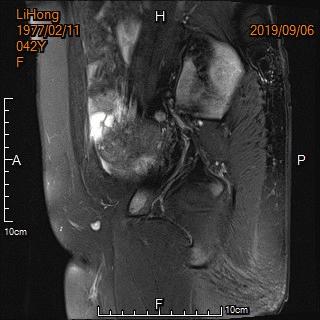

中年女性,反复痛经、经期延长5年余。确诊为子宫腺肌症,经妇科保守治疗症状无改善,病情进行性加重。

术前MRI显示子宫明显增大

术前MRI显示子宫明显增大,病灶主要位于子宫后壁